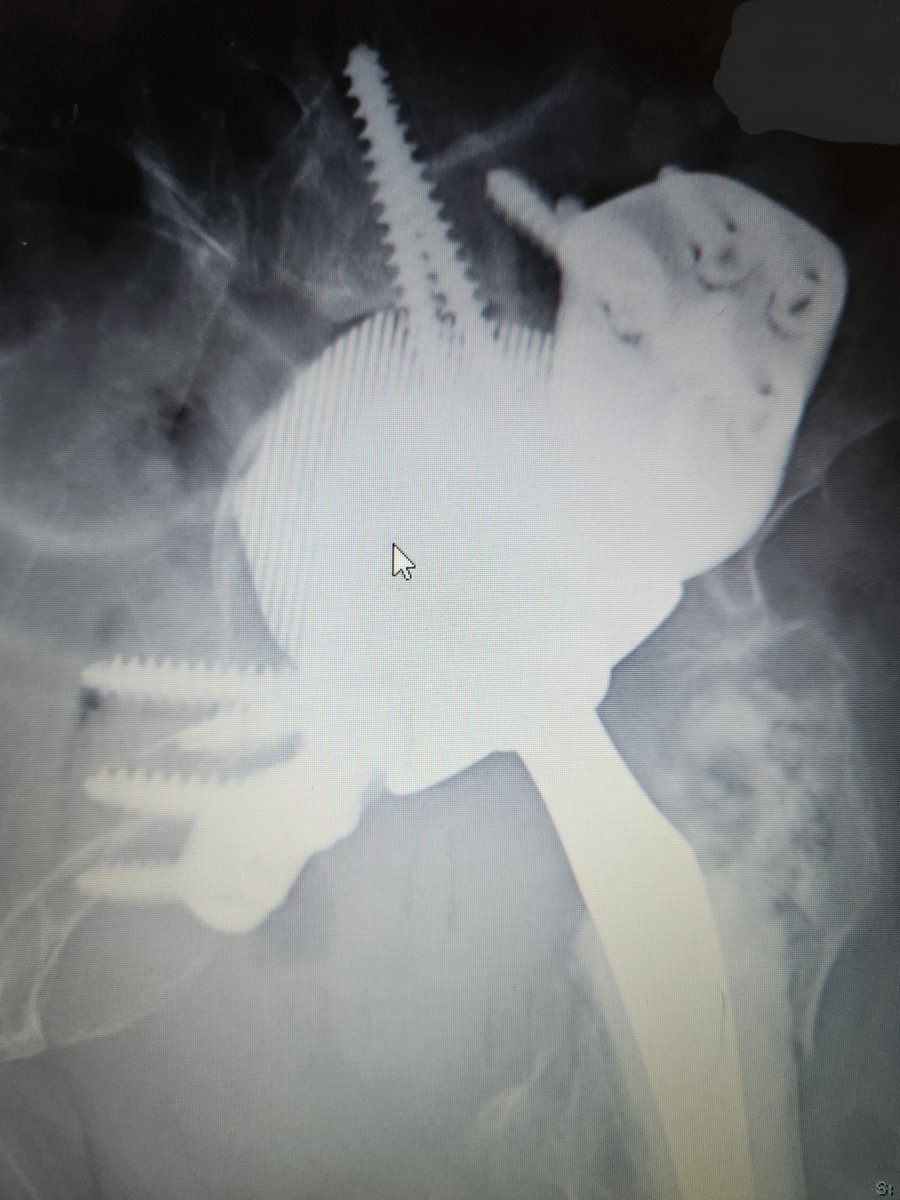

These are expensive too and a lot of hard work goes into getting pt on table. Thank you to YGC theatres & staff for the effort, @BetsiCadwaladr for support, fantastic MDT Wrightington, North Wales MDT, surgical experience @CavendishHip, my colleagues & Mr Kapur for dual operating